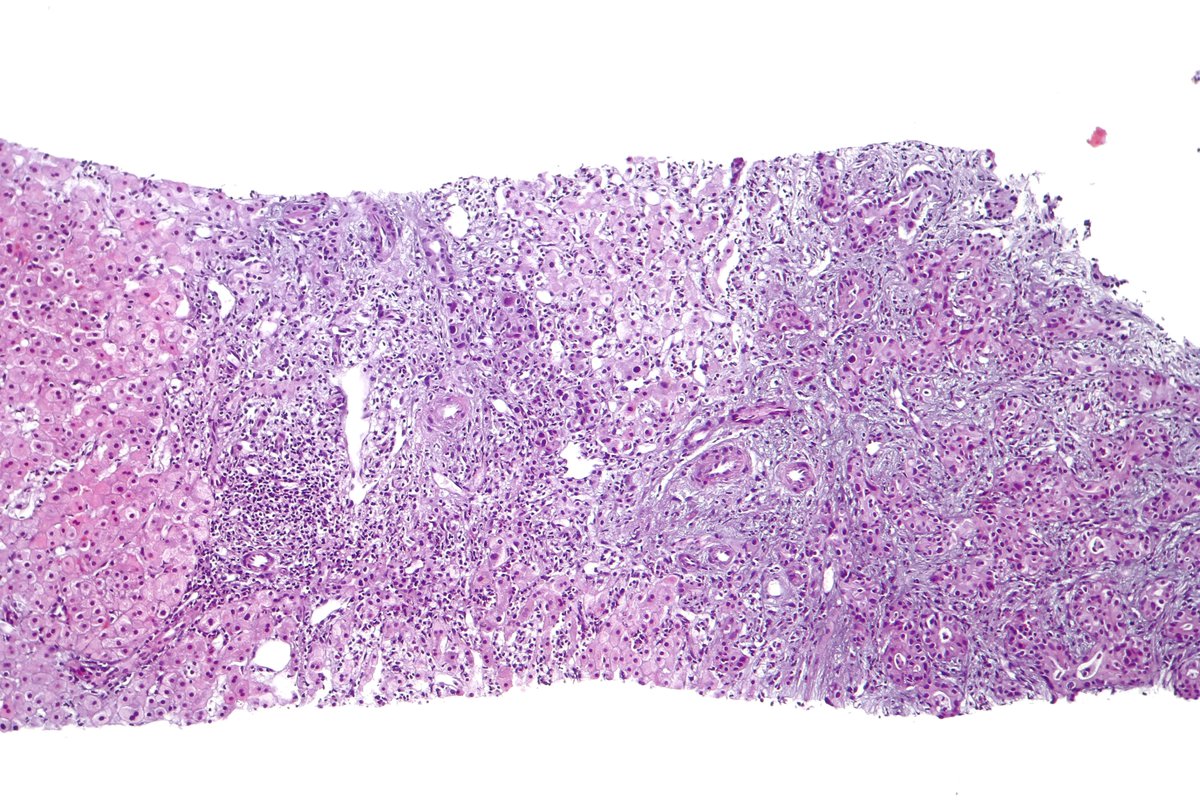

Type B2 Thymoma showing prominent large epithelial cells admixed with numerous lymphocytes. #pathology #PulmPath